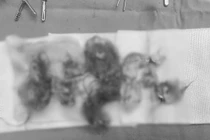

u-quai-3.png

Hình ảnh khối u quái buồng trứng chứa tóc, xương và răng - Ảnh BVCC

Thông qua 3 đường rạch nhỏ chưa đến 1cm, các bác sĩ đã từng bước đưa dụng cụ nội soi vào ổ bụng, loại bỏ hoàn toàn khối u và 2 phần phụ. Khi tách khối u, ê-kíp phát hiện bên trong chứa tóc, xương và cả mảnh răng nhỏ – đúng với đặc điểm điển hình của u bì trưởng thành.